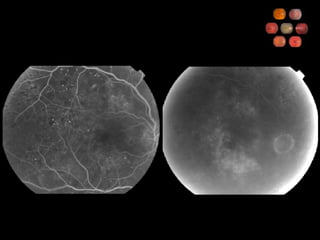

60 yo  Scotoma for  one wk

Ocular Ischemic Syndrome What percent carotid obstruction is typically required to cause OIS? 90% Describe the symptoms Gradual visual loss Aching pain Prolonged recovery following bright light exposure What are anterior segment findings? Iris neovascularization (67%) AC cellular reaction (20%)

Ocular Ischemic Syndrome Describe the posterior segment findings Narrowed arteries Dilated, non-tortuous veins Mid-peripheral retinal hemorrhages, microaneurysms Neovascularization What are the fluorescein angiographic findings? Delayed choroidal filling (60%)  Delayed arteriovenous transit (95%) Vascular staining (85%) What is the 5-year mortality rate and what is the most common cause of death? 40% Cardiovascular disease

Ocular Ischemic SyndromeWhat percent carotid obstruction is typically required to cause OIS? 90% Describe the symptoms Gradual visual loss Aching pain Prolonged recovery following bright light exposure What are anterior segment findings? Iris neovascularization (67%) AC cellular reaction (20%)

Ocular Ischemic SyndromeDescribe the posterior segment findings Narrowed arteries Dilated, non-tortuous veins Mid-peripheral retinal hemorrhages, microaneurysms Neovascularization What are the fluorescein angiographic findings? Delayed choroidal filling (60%) Delayed arteriovenous transit (95%) Vascular staining (85%) What is the 5-year mortality rate and what is the most common cause of death? 40% Cardiovascular disease